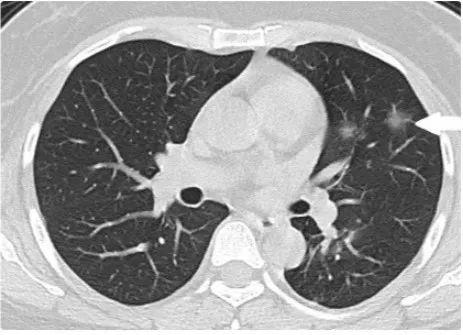

新型冠壮病毒自爆发以来,全球范围内都对其进行了广泛而深入的研究,随着病毒变异和防控措施的调整,其最新状态也引发了社会各界的关注,本文旨在探讨新型冠壮病毒的最新状态,分析当前形势下的正反方观点,并提出个人的立场及理由。

另一些观点则持谨慎态度,病毒在不断变异,一些变异株的传染性和致病性可能更强,全球疫苗接种率不平衡,许多地区和人群尚未得到充分的保护,加之国际旅行和人员流动的增加,病毒传播的风险仍然存在,反方观点认为,新型冠壮病毒的防控形势依然严峻。

个人认为,当前新型冠壮病毒的防控形势依然严峻,需要我们保持警惕,虽然全球疫苗接种率不断提高,但病毒变异和全球接种不平衡的问题仍然不容忽视,我们还需要重视个人防护和社交距离等防控措施,以减轻病毒传播的风险。